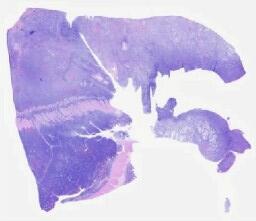

临床资料: 男,7岁,间断腹泻1年余病程:反复腹泻1年,黄色稀糊便,每日2-3次,偶达4-5次,伴脐周痛,口服益生菌效果有限。7个月前因粘液脓血便、发热住院,诊断为沙门菌感染、结肠炎症,予美罗培南等治疗后好转,但出院后仍反复发作。近半月大便糊状,无血丝,无便血或黑便,无呕吐及腹痛。既往史:急性淋巴细胞白血病:2018年11月确诊,2021年接受CAR-T治疗,目前完全缓解;无传染病、手术外伤史,否认消化系统疾病史;无药物或食物过敏。